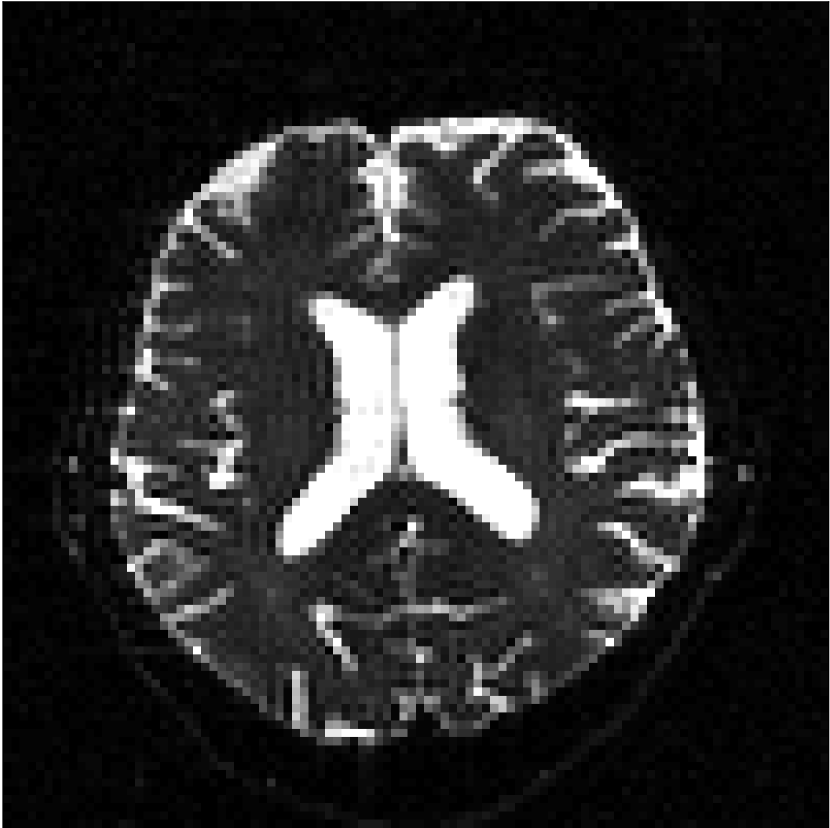

Figure 10 compares mean diffusivity maps across various partial Fourier factors between the CCNN and state-of-the-art methods.

No PF

7/8 PF

6/8 PF

5/8 PF

SoA

Refer to caption

MD, μ𝜇\mum2/ms

CCNN

Figure 10: Comparison of mean diffusivity (MD) parameter maps across PF factors of 5/8ths, 6/8ths, 7/8ths, and without PF (No PF). The methods include state-of-the-art (SoA) and CCNN methods. Without partial Fourier, both methods are similar; however, as the PF factor increases, substantial artifacts are introduced in the SoA method, particularly around the lateral ventricles. The CCNN method is able to reduce the introduction of artifacts.

The methods perform similarly without partial Fourier acceleration, but as partial Fourier acceleration increases, the image is continually degraded in the SoA method, with "black voxels" appearing around the lateral ventricles. The CCNN method mitigates the appearance of these artifacts in the parameter maps.